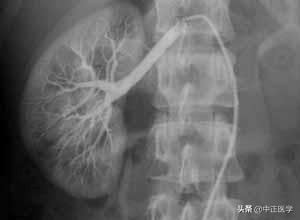

造影检查种类很多,可分为支气管造影、钡剂灌肠检查、口服胆囊造影、胃肠钡餐造影、静脉尿路造影、子宫输卵管造影、经皮肤穿刺胆道造影,心脏和动脉造影。造影检查是将一种比人体密度高或低的物质导入到人体内要检查的部位,人工地造成要检查部位密度差异,以构成对比,达到诊断的目的。